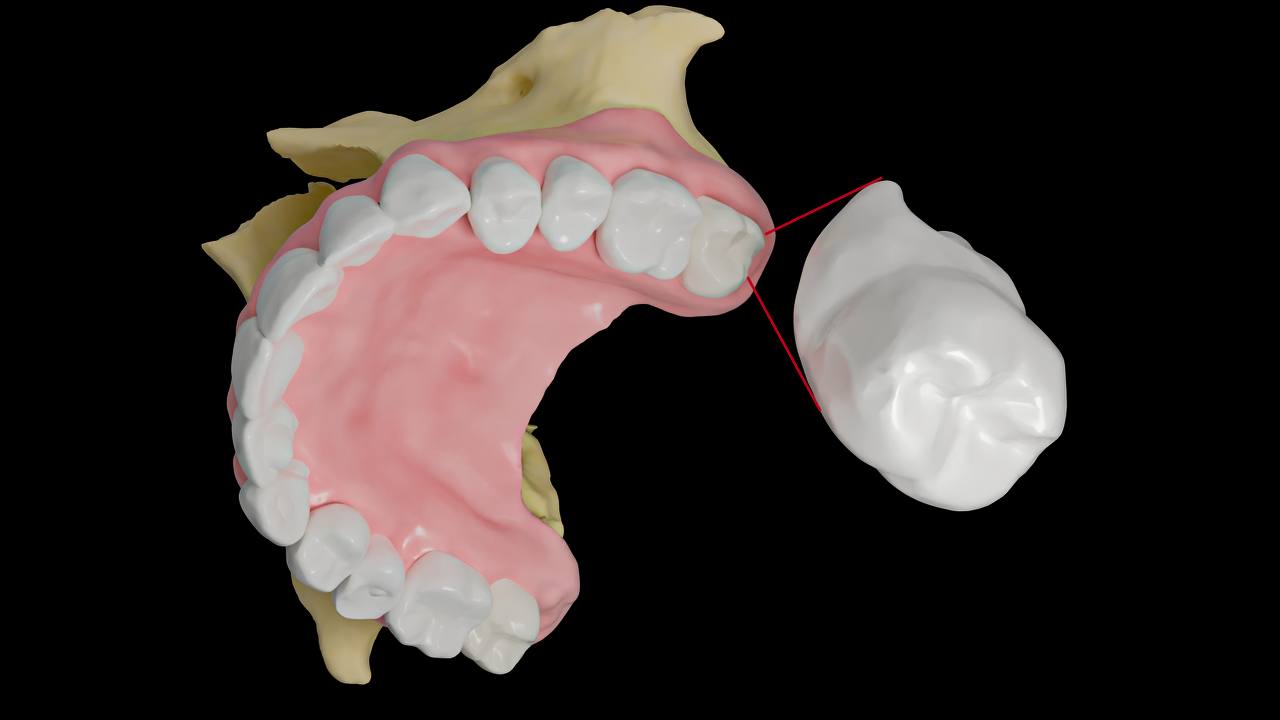

Удаление зубов мудрости в верхней и нижней челюсти имеет свои особенности, обусловленные анатомическими различиями и положением этих зубов.

Удаление зубов мудрости на верхней челюсти

Анатомические особенности:

Зубы мудрости в верхней челюсти расположены как правило близко к дну гайморовой пазухи, в некоторых случаях – непосредственно в ней. Чтобы не повредить ее, врач может принять решение ушить расстояние между лункой и пазухой.